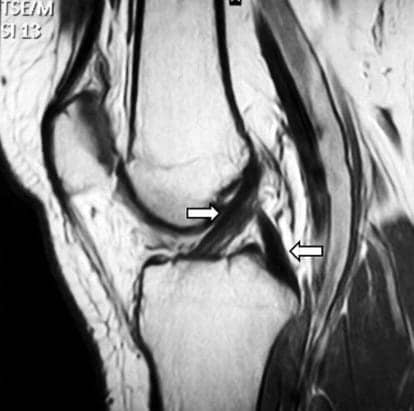

Assim, o Comitê Olímpico Internacional buscou os principais pesquisadores da área para estudar as melhores formas de predizer essa lesão. Dentre as possibilidades encontradas, foi indicada a utilização do teste drop jump para identificar possíveis alterações do joelho durante a fase de aterrissagem. Por meio da análise cinemática desse salto pode-se identificar alguns fatores preditores de lesão do ligamento cruzado anterior, como: ângulo valgo do joelho, momento de abdução do joelho, ângulo de flexão do joelho e deslocamento medial do joelho.

A força de reação do solo também é um importante parâmetro de avaliação de assimetria e compensações exercidas pelos membros inferiores em relação à superfície de apoio. Para esse tipo de análise, o drop jump é o teste de salto mais utilizado. Quando se fala de população a ser avaliada com essas características, destacam-se os pacientes com lesão no ligamento cruzado anterior (LCA). Esses pacientes, mesmo após cirurgia e retorno ao nível de atividade pré-lesão, costumam exibir consideráveis assimetrias nos membros inferiores durante os movimentos unilaterais e bilaterais.

Baumgart et al. (2017) confirmaram essa informação ao avaliar pacientes pós-cirúrgicos de LCA com baixa consistência durante a recuperação, verificando valores de força de reação do solo mais baixos em comparação à população normal e maiores assimetrias de força de reação do solo. Com isso, sugere o uso de estratégias de compensação para o membro não lesionado. Assim, a utilização do drop jump em conjunto com as variáveis extraídas da plataforma de força representa uma informação relevante para a melhor reabilitação desses pacientes.